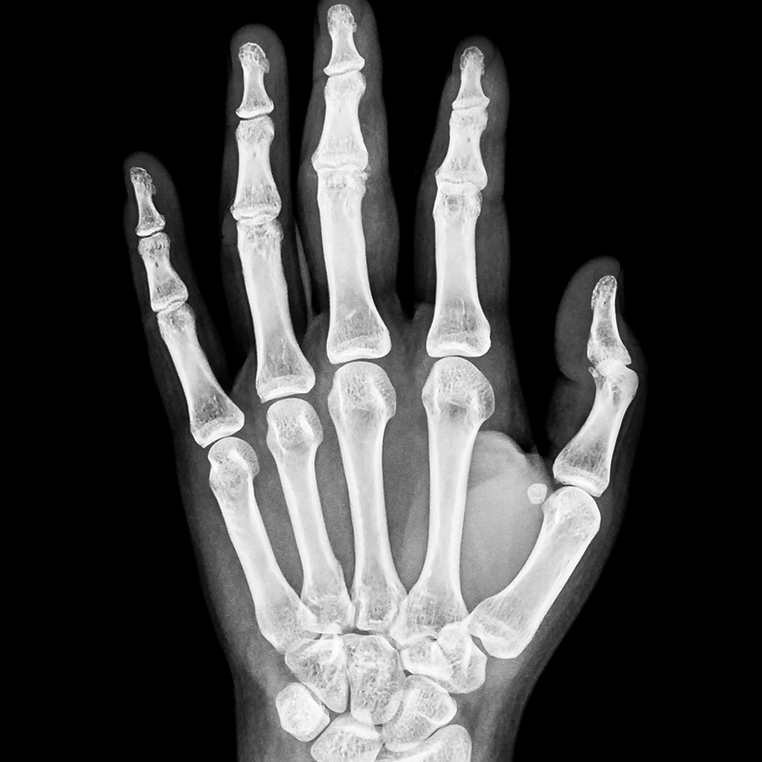

서울퍼펙트의 영상의학 검사는 먼저 방사선검사로 확인하며, 다른 질환으로 인한 증상은 아닌지 확인합니다. 결절종은 초음파로 대부분 진단 가능합니다.

먼저 물혹이 생긴 위치나 모양을 관찰합니다. 대부분의 결절종은 동그랗고 부드러우며 단단하지만 움직임이 있습니다. 수술 경험이 많은 전문의의 경우, 물혹을 만져보고 육안으로 보기만 해도 대부분 결절종인지 아닌지를 감별할 수 있습니다. 그리고 더 자세한 진단을 위해서 X-ray 검사와 초음파 검사를 시행합니다.